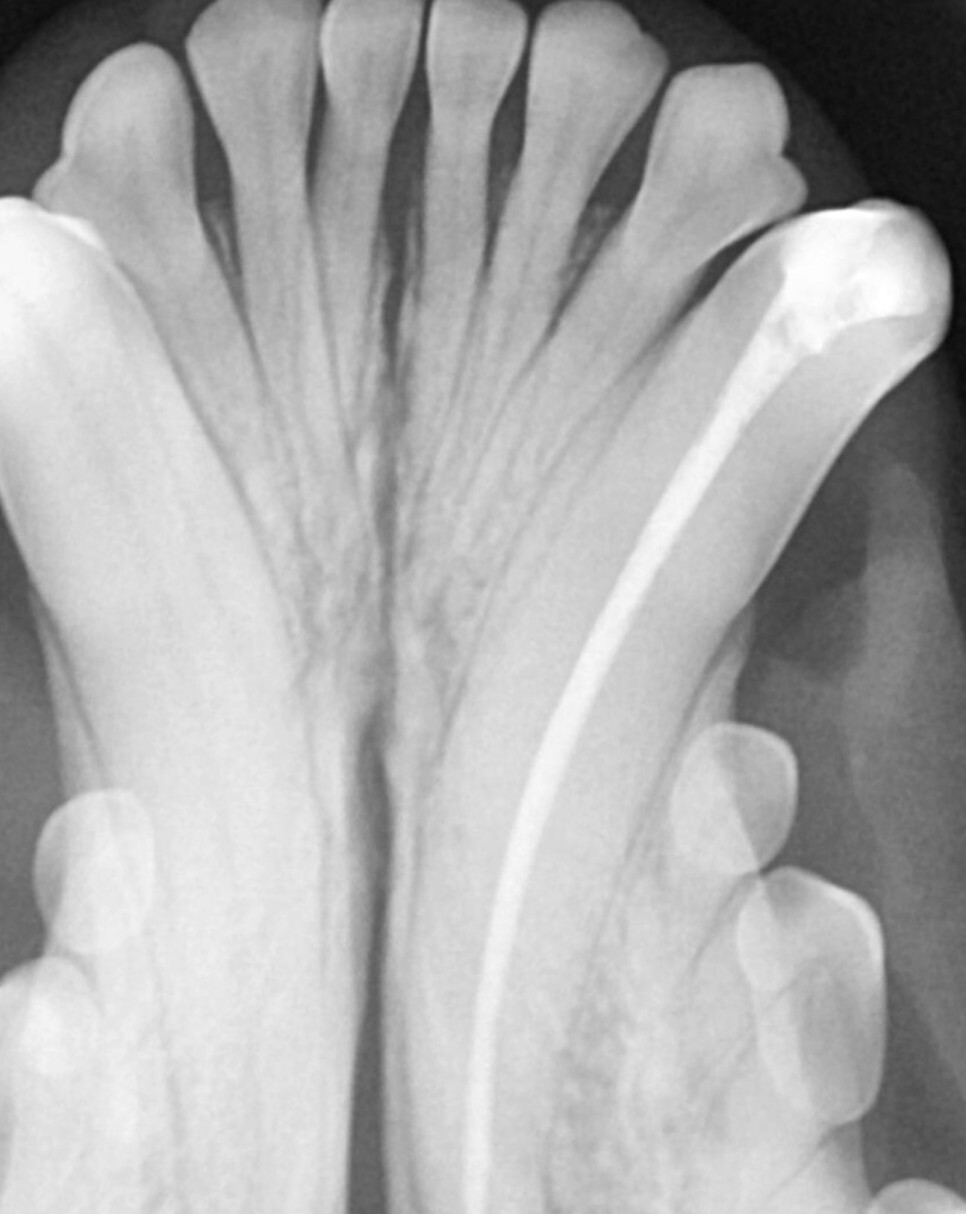

근관치료는 감염된 치수를 제거하고 충진 재가

잘 들어갈 수 있도록 근관을 형성, 소독 후

생체 친화적인 물질을 이용하여 치수강을 채워

밀봉하는 순서로 진행합니다.

치료 이후에는 감염의 징후가 있는지 확인을

위해 6개월~1년 후에 치과 방사선 촬영이 필요합니다.

이때에도 마취가 필요하기 때문에 치아골절 치료

방향을 결정할 때는 동물의 건강 상태, 치아의 중요

도 등을 고려해야 합니다.